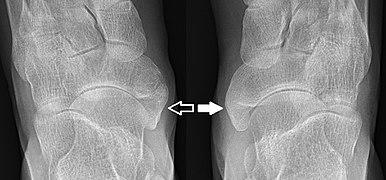

Os tibiale externum - Roe Fuss.jpg

X-ray of the foot showing an accessory navicular bone

An accessory navicular bone is an accessory bone of the foot that occasionally develops abnormally in front of the ankle towards the inside of the foot. This bone may be present in approximately 2-21% of the general population and is usually asymptomatic.[1][2][3] When it is symptomatic, surgery may be necessary.

The Geist classification divides the accessory navicular bones into three types.[3]

• Type 1: An os tibiale externum is a 2–3 mm sesamoid bone in the distal posterior tibialis tendon. Usually asymptomatic.

• Type 2: Triangular or heart-shaped ossicle measuring up to 12 mm, which represents a secondary ossification center connected to the navicular tuberosity by a 1–2 mm layer of fibrocartilage or hyaline cartilage. Portions of the posterior tibialis tendon sometimes insert onto the accessory ossicle, which can cause dysfunction, and therefore, symptoms.

• Type 3: A cornuate navicular bone represents an enlarged navicular tuberosity, which may represent a fused Type 2 accessory bone. Occasionally symptomatic due to bunion formation.